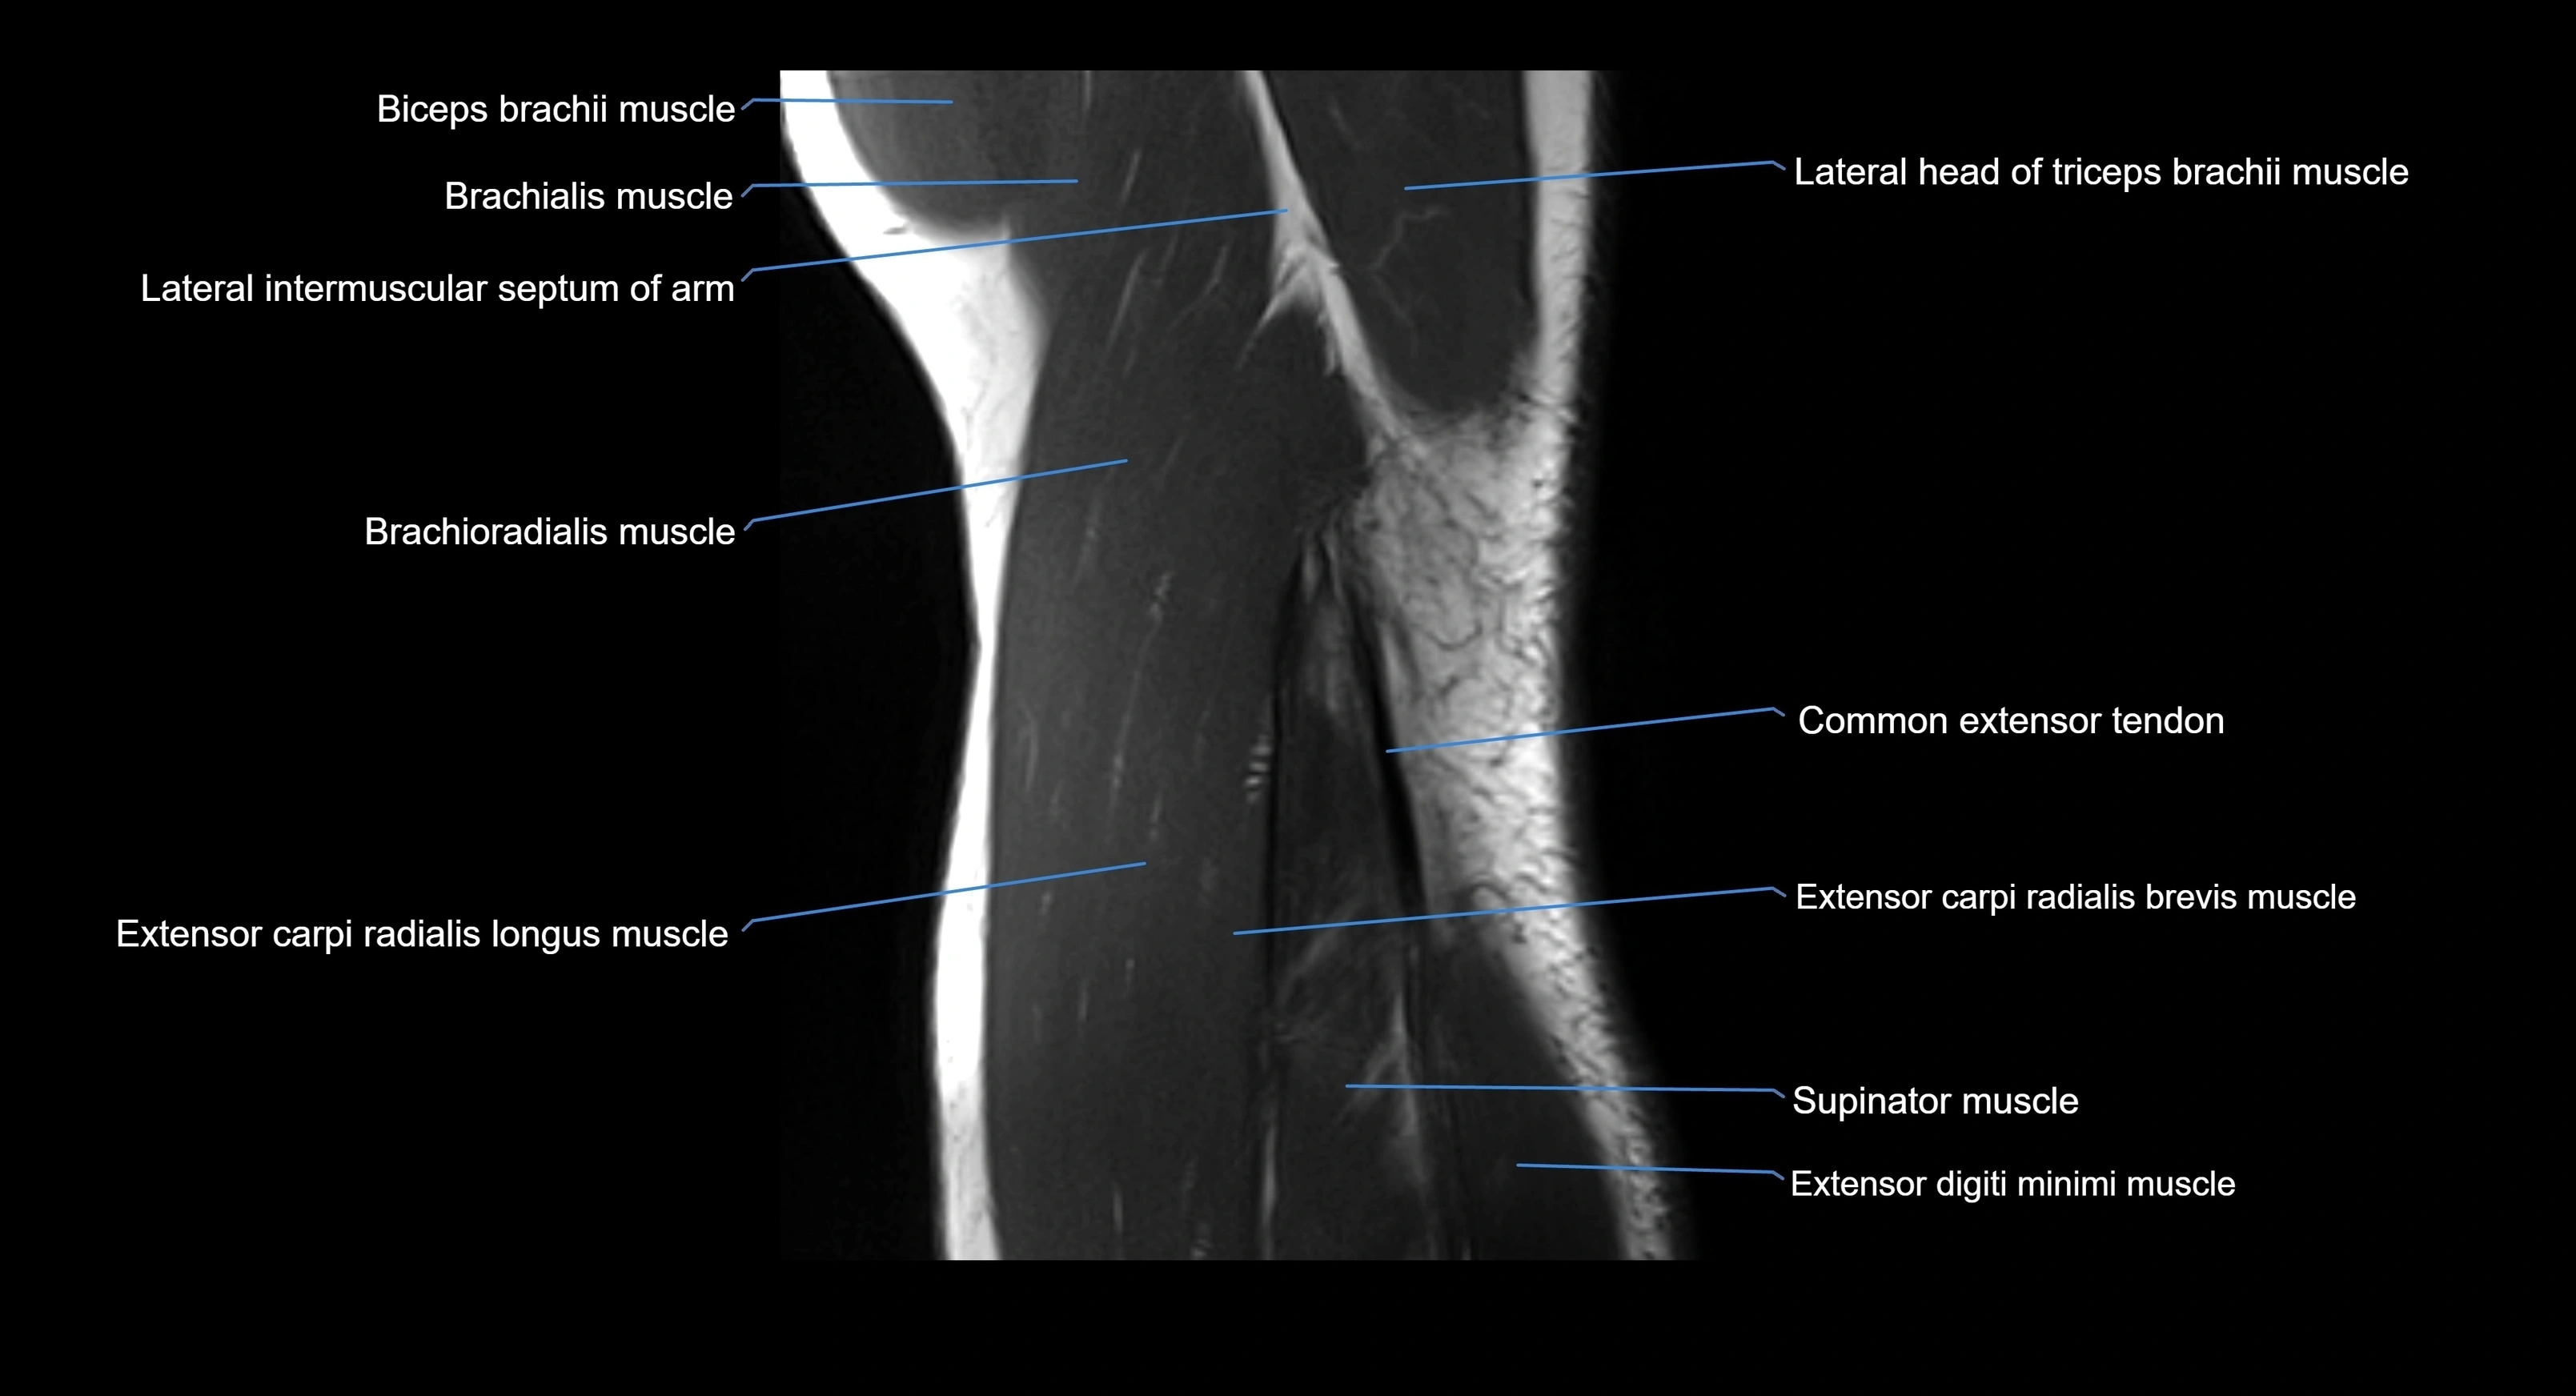

MRI image

image